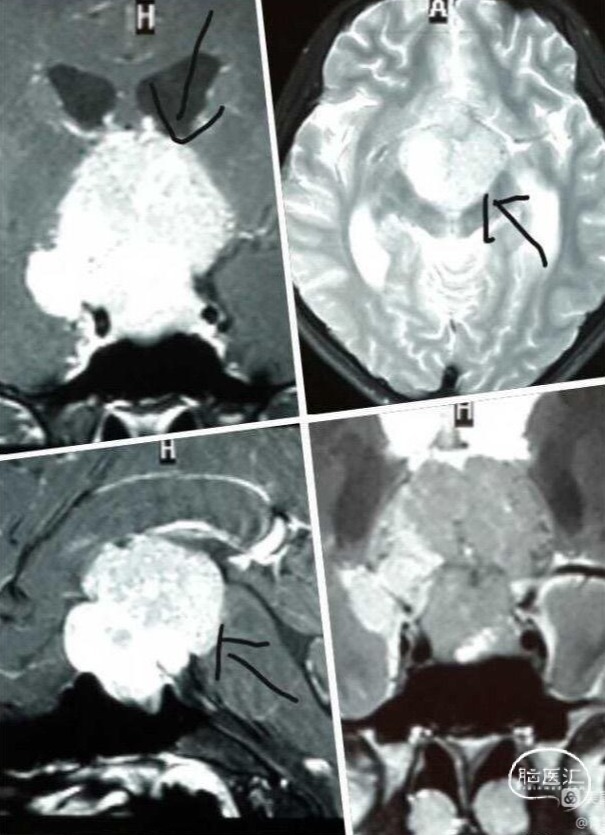

图为门诊的部分病例,说好的"养生手术"难见踪影。😍😃